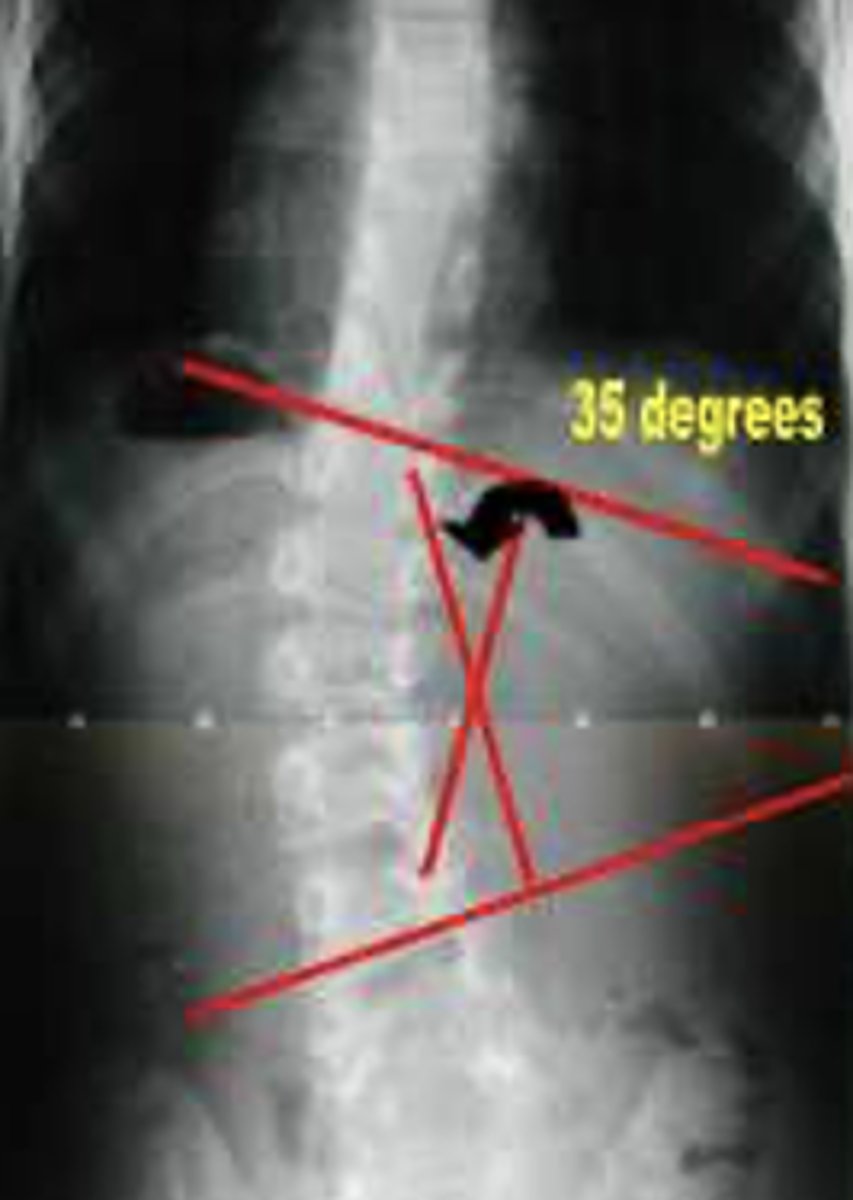

Cobb Angle

Measured to define scoliosis. > 10° is needed for dx.

•Cobb Angle